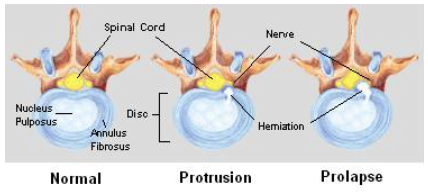

These injuries can occur with extreme compressive, forward-bending, and rotating forces such as car accidents. The disc is a structure in the spine which helps with shock absorption and mobility through the back. When a disc herniation occurs, the inner content (nucleus pulposus) of the disc will move outwards from the more solid outer layer (annulus fibrosus) (image 1). In more severe injuries, the inner content can compress on structures such as the spinal cord (image 2). Some symptoms experienced for this issue include pain traveling down the leg, difficulty bending down and back pain.

Image 1. A bird’s eye view of a disc herniation. Source.

As seen in image 1, the spinal cord (yellow) sits within the spine. Its main role is to relay messages from the brain to the body and vice versa. These roles include vital pieces of information such as movement, sensation and reflexes. Spinal cord injuries can be caused by trauma, such as car accidents and falls. Depending on the location and severity, symptoms will vary substantially. For example, partial spinal cord injuries may result in a loss of sensation in a single leg. In comparison, a complete spinal cord injury can result in paralysis and complete loss of feeling down the legs.